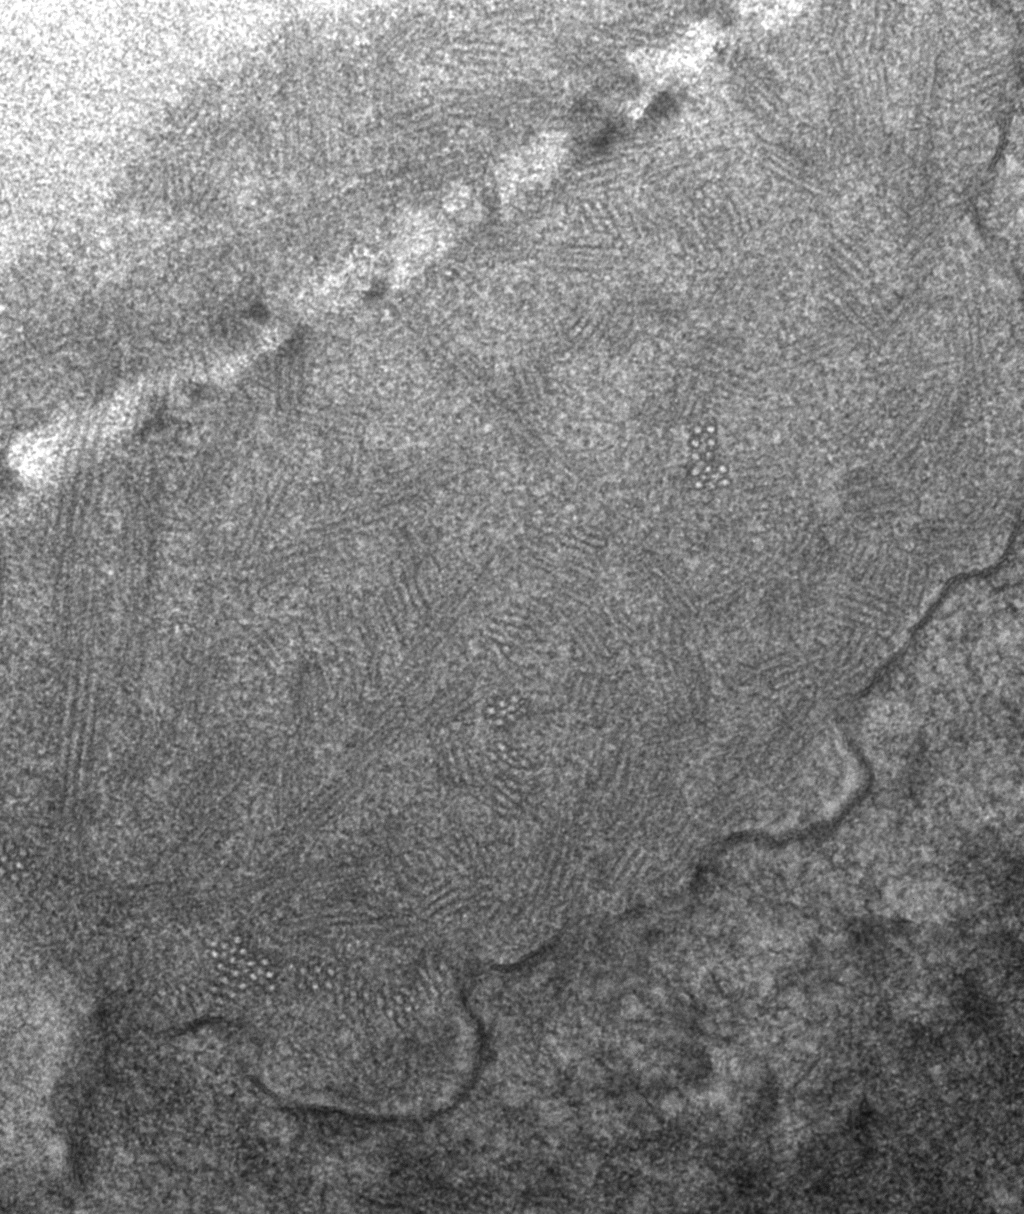

- 0.3cm - 0.5cm of cortex with glomeruli for glutaraldehyde, EM

Acceptable alternatives to 2% Phosphate buffered Glutaraldehyde for electron microscopy